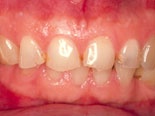

Före och efter behandling med fyra keramiska skalfasader.

Före och efter behandling med kompositfasader.

Sex keramiska skalfasader, före och efter behandling. Samtliga tänder är blekta.